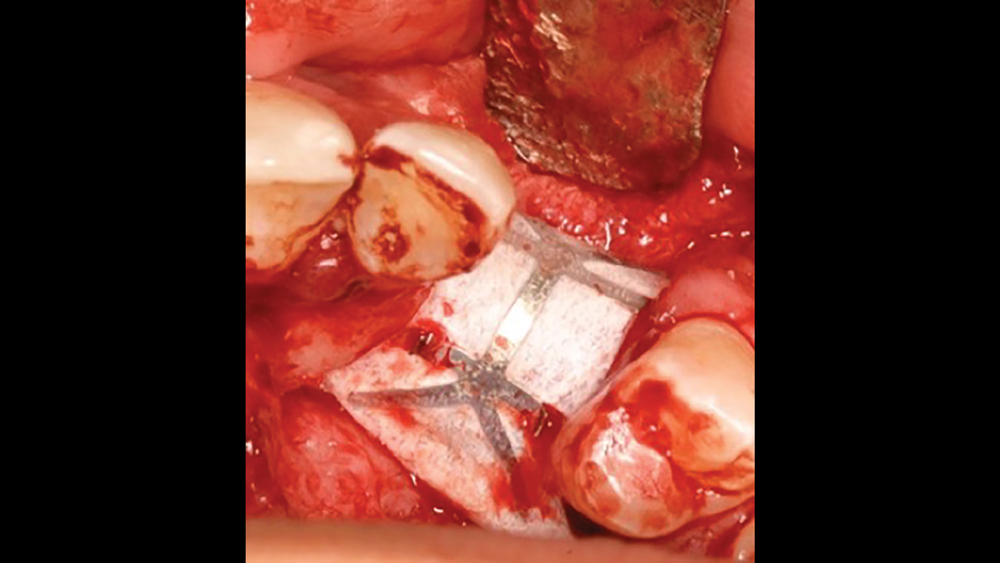

Titanium Mesh Membranes

Titanium mesh is a non-resorbable membrane that has been shown to be effective in maintaining space without collapsing. The membranes are flexible and can be bent and manipulated to form around the bony defect. The titanium mesh has demonstrated biocompatibility and features holes within the mesh, which allow for maintaining blood supply from the periosteum. The disadvantages of titanium mesh are increased wound dehiscence and difficulty in maintaining soft-tissue coverage (Figs. 4a, 4b). This may lead to increased infection and patient discomfort, which could lead to the necessity for early removal.

Figure 4a: Titanium mesh membranes have holes incorporated within the mesh

Figure 4b: Mesh exposure

Figures 4a, 4b: Titanium mesh membranes have holes incorporated within the mesh (4a), which allow for maintaining blood supply; however, these membranes have the disadvantage of increased wound dehiscence, which commonly involves exposure of the mesh (4b).